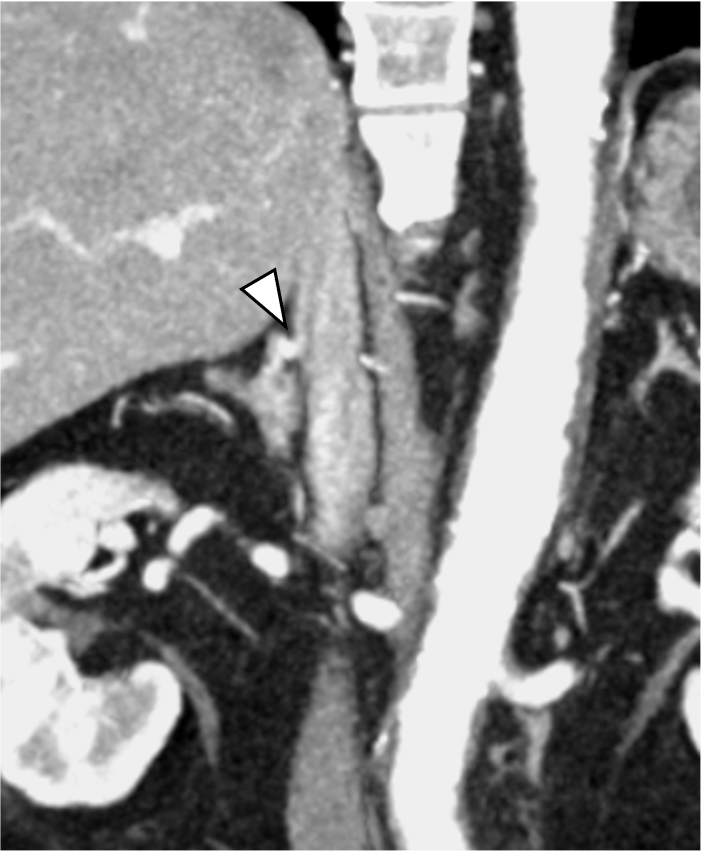

当該疾患の診断における造影CTの役割

原発性アルドステロン症は, 治癒可能な二次性高血圧であり, 本態性高血圧より脳・心血管, 腎合併症の頻度が高く, その診断および治療の重要性が指摘されている, 片側性のアルドステロン症の場合, 外科的切除によりアルドステロン過剰の正常化, 高血圧および臓器障害の改善・防止が期待できる, このため, 手術が考慮される場合には副腎静脈サンプリングによる機能的局在診断を行う, 原発性アルドステロン症診療ガイドライン20211)では, この副腎静脈サンプリングの成功率を向上させる方法の一つとして, ダイナミックmulti-detector row CT(MDCT)が推奨されている, MDCTでは, 横断像やMPR(Multi planar Reconstruction)を用いて, 副腎静脈の走行やvariationの確認などを行うが, これに加え当院では,仮想透視画像を作成し, 右副腎静脈の下大静脈開口部のレベルや, 副肝静脈との位置関係など, 立体的な解剖学的把握を行っている, その結果, サンプリング時に, スムーズかつ的確なカテーテル操作が可能となる.

注意点としては, CTでは深吸気時に撮影されるのが一般的であるが, カテーテル操作は, 安静呼吸下で施行されるため, 副腎静脈の位置がやや異なることがある. 当院では, 呼吸性変動を踏まえて, 後期動脈相, 門脈優位相を呼気にて撮影し, 平衡相のみ吸気にて撮影している.

本検査における後期動脈相は, 右副腎静脈と下大静脈との合流部, また左副腎静脈と下横隔静脈, 腎静脈との合流部の形態評価が求められる重要な撮影時相である. そのため30sec注入時間固定法とbolus tracking法の併用を行い, 腹部下行大動脈において+100HUのCT値上昇をトリガーとし, 20secのdelay timeにて後期動脈相の撮影を行っている. その後の門脈優位相は, トリガーから40secの撮影とし, 主に副肝静脈と下大静脈との合流部の形態評価が目的とされる. 造影コントラスト向上のため. 可能な限り低管電圧撮影が行えるよう留意している. なお, 本症例は, 造影剤量がプロトコルより少ない症例であったが, 低管電圧撮影や後期動脈相の最適な撮影タイミングにより, 副腎静脈を良好に描出し得た.